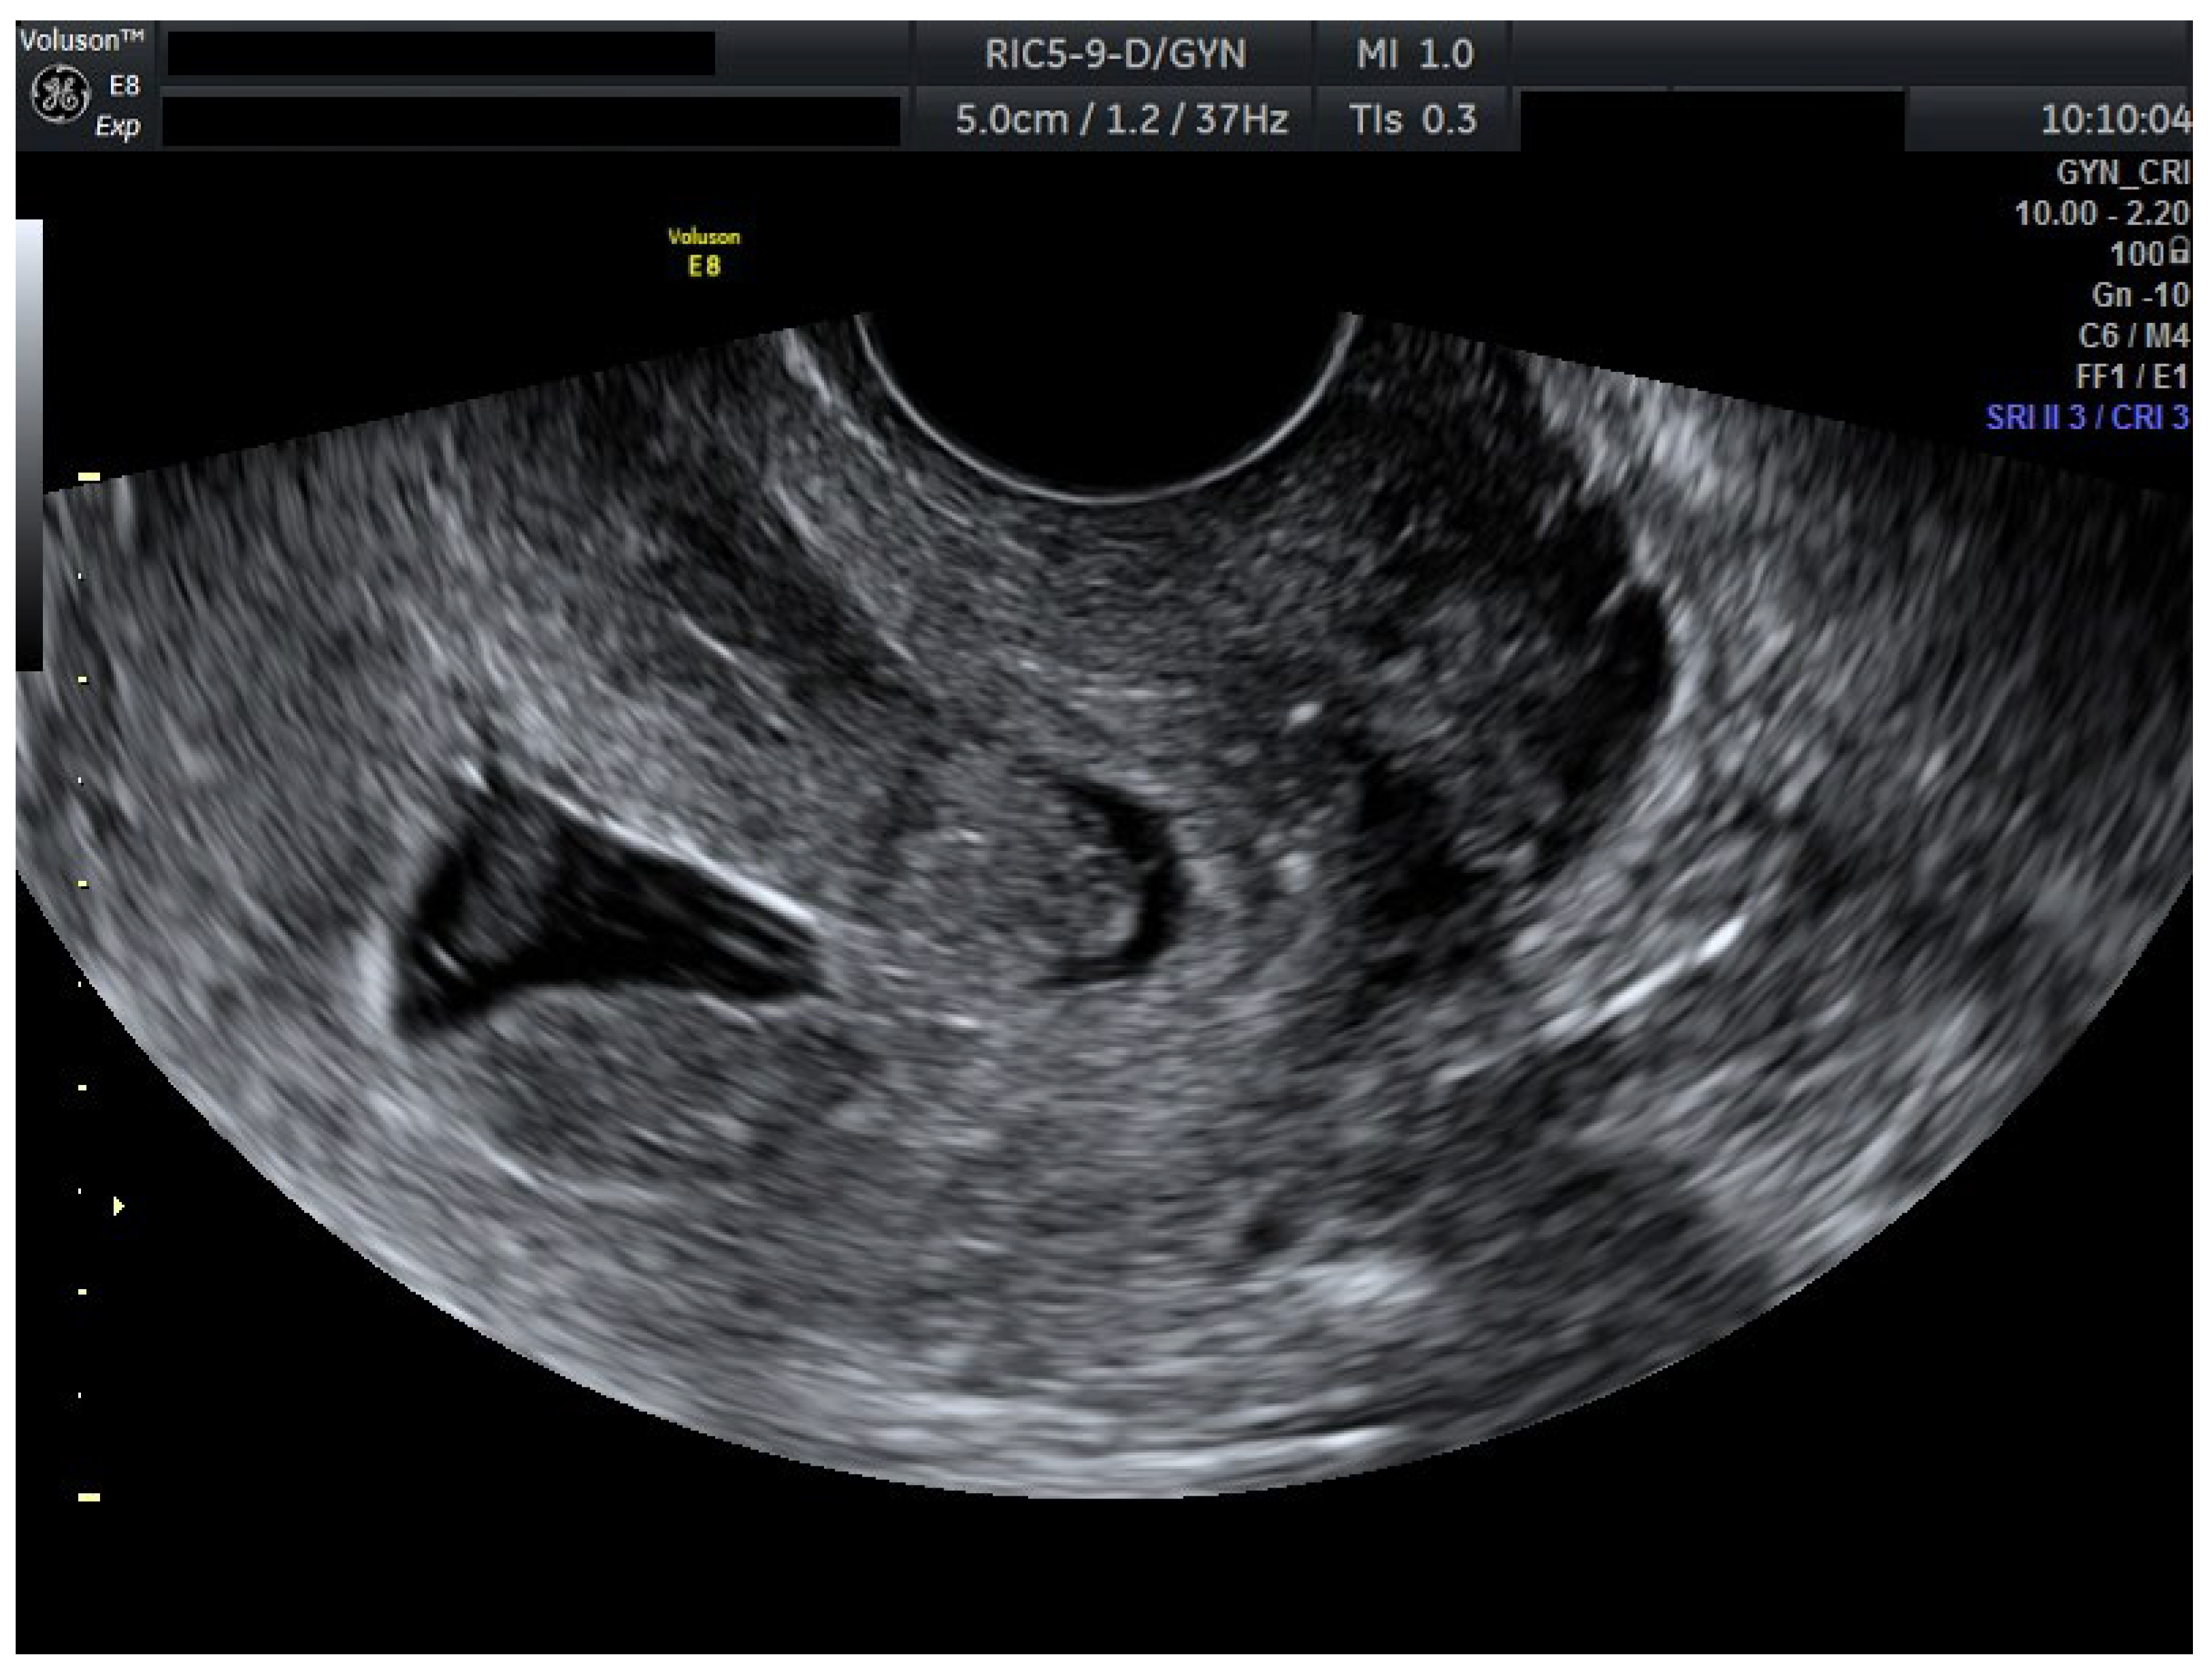

To ensure complete trophoblastic regression in both pregnancies, systemic methotrexate 100 mg was administered intramuscularly at this time (Day 4). A follow-up ultrasound at 48 h (Day 6) confirmed the absence of cardiac activity in both gestations, disorganized gestational sacs, consistent with successful termination. Cervical stromal vascularity identified on color Doppler was suggestive for trophoblastic remnants (Figure 2).

Figure 2.

Ultrasound results after methotrexate 100 mg (Day 6). Transvaginal ultrasound evaluation: both sagittal view through the uterus and transverse view through the cervical canal. A total of 48 h after methotrexate 100 mg (Day 6): both embryos without cardiac activity. Cervical stroma with vascularity. Patient information is anonymized.

Serial ultrasound over 72 h documented progressive closure of feeding vessels and reduction in cervical stromal vascularity.